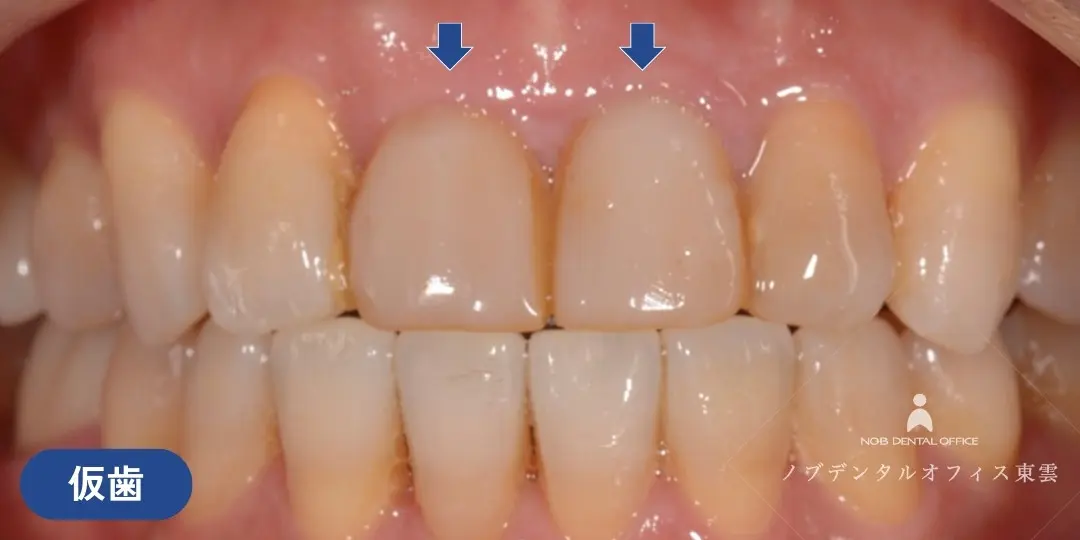

前歯をブリッジで治療した症例(40代女性)

上の前歯2本を失い、仮歯が入っている状態でした。

インプラント・ブリッジ・入れ歯の治療計画をお話しさせていただき、治療期間やリスク、強度や審美性を踏まえて、ブリッジ治療を行いました。

両隣の歯はいずれも神経がなく歯質が薄い状態でした。歯の根のトラブルが起きるとブリッジを取り外すことになってしまうので、補強もかねて根管治療の再治療を行ない、ブリッジの支台歯にしました。

セラミック完成前に仮歯に置き換え、見た目・発音・噛み合わせを調整した上で、セラミックのブリッジを作製しました。

前歯の目立つ場所でしたが、ジルコニアのブリッジで自然な仕上がりになっています。